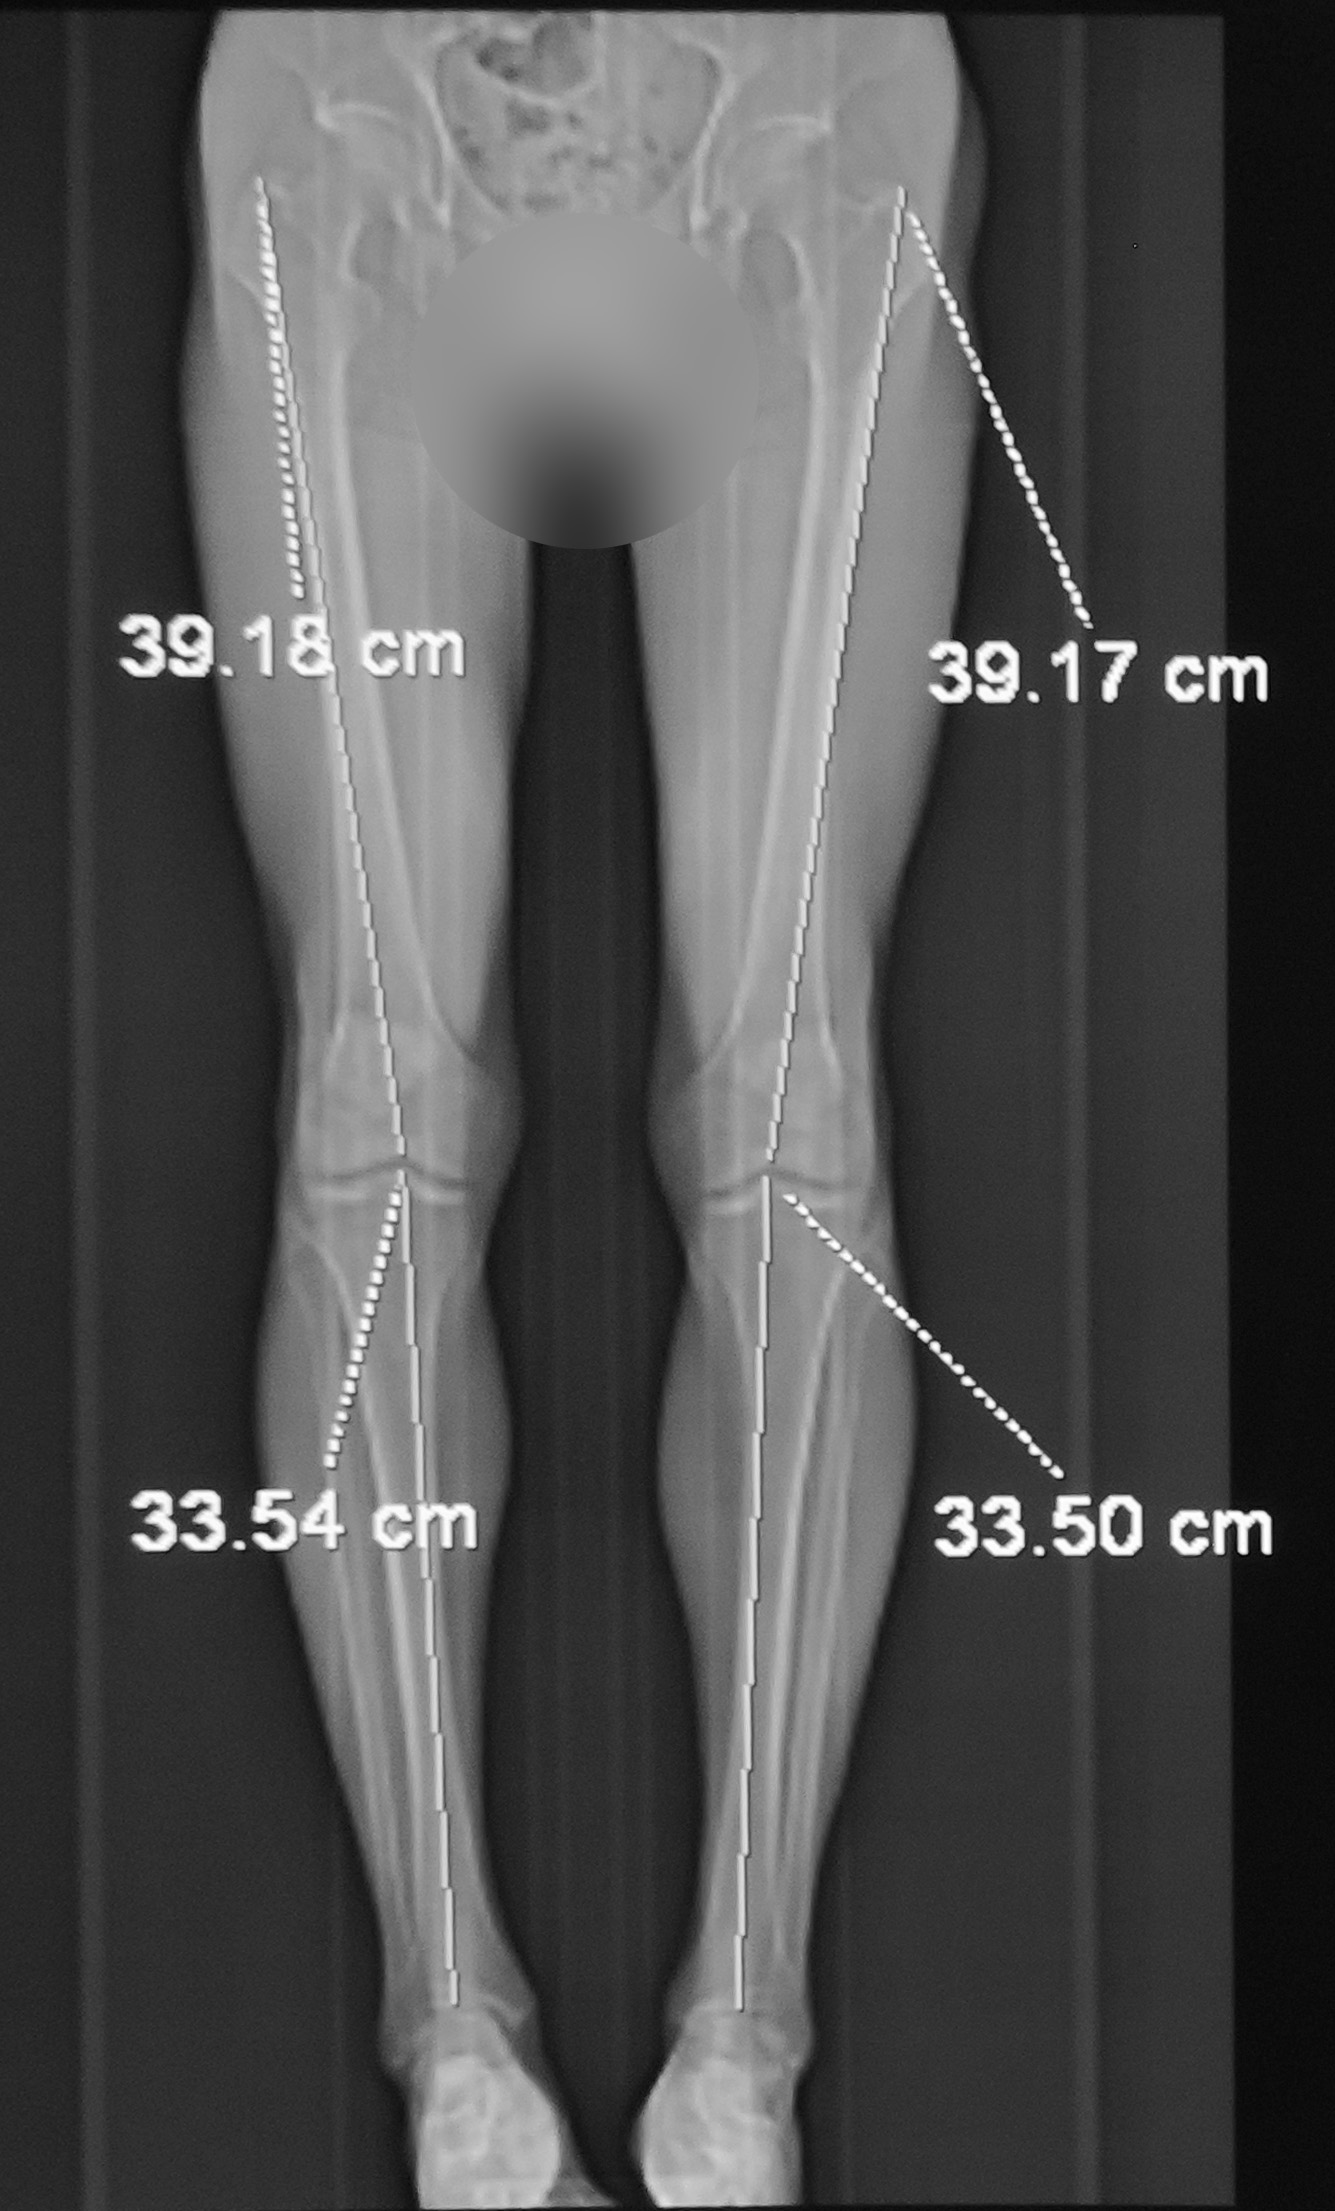

To be short, I underwent 3 surgeries and finished treatment with 4 implants in legs within 6 months. I attached 2 CT scans – before and after with 4 implants. I will lie if I say the treatment was an easy procedure. There are days when the pain is stronger than average but I could manage it by taking painkillers, do physical exercises. By the way, I had a physical therapy 6 times a week․ I worked with the physical therapist for one hour, but continued doing exercises, walking a few times a day. Honestly, it was hard but I realized the difficulties and more important, it was my decision to become taller.